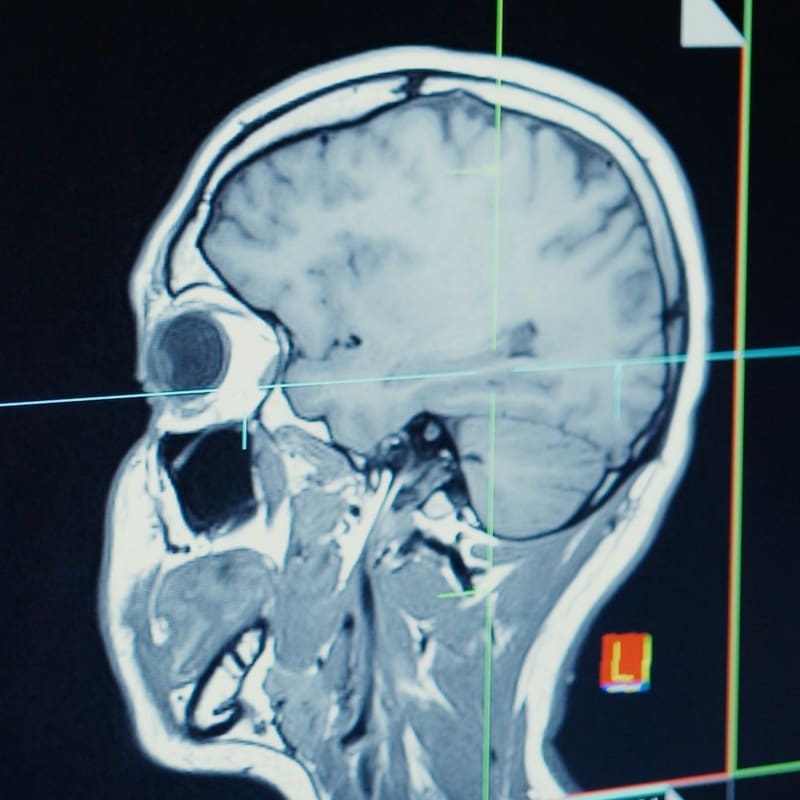

En una investigación publicada en Nature Aging, científicos del Reino Unido y China examinaron datos de casi 500.000 adultos de entre 38 y 73 años del Biobanco del Reino Unido. Se preguntó a los participantes sobre sus patrones de sueño, salud mental y bienestar, y participaron en una serie de pruebas cognitivas. Las imágenes del cerebro y los datos genéticos estaban disponibles para casi 40.000 de los participantes del estudio.

El equipo también encontró un vínculo entre la cantidad de sueño y las diferencias en la estructura de las regiones del cerebro involucradas en el procesamiento cognitivo y la memoria, nuevamente con mayores cambios asociados con más o menos de siete horas de sueño.